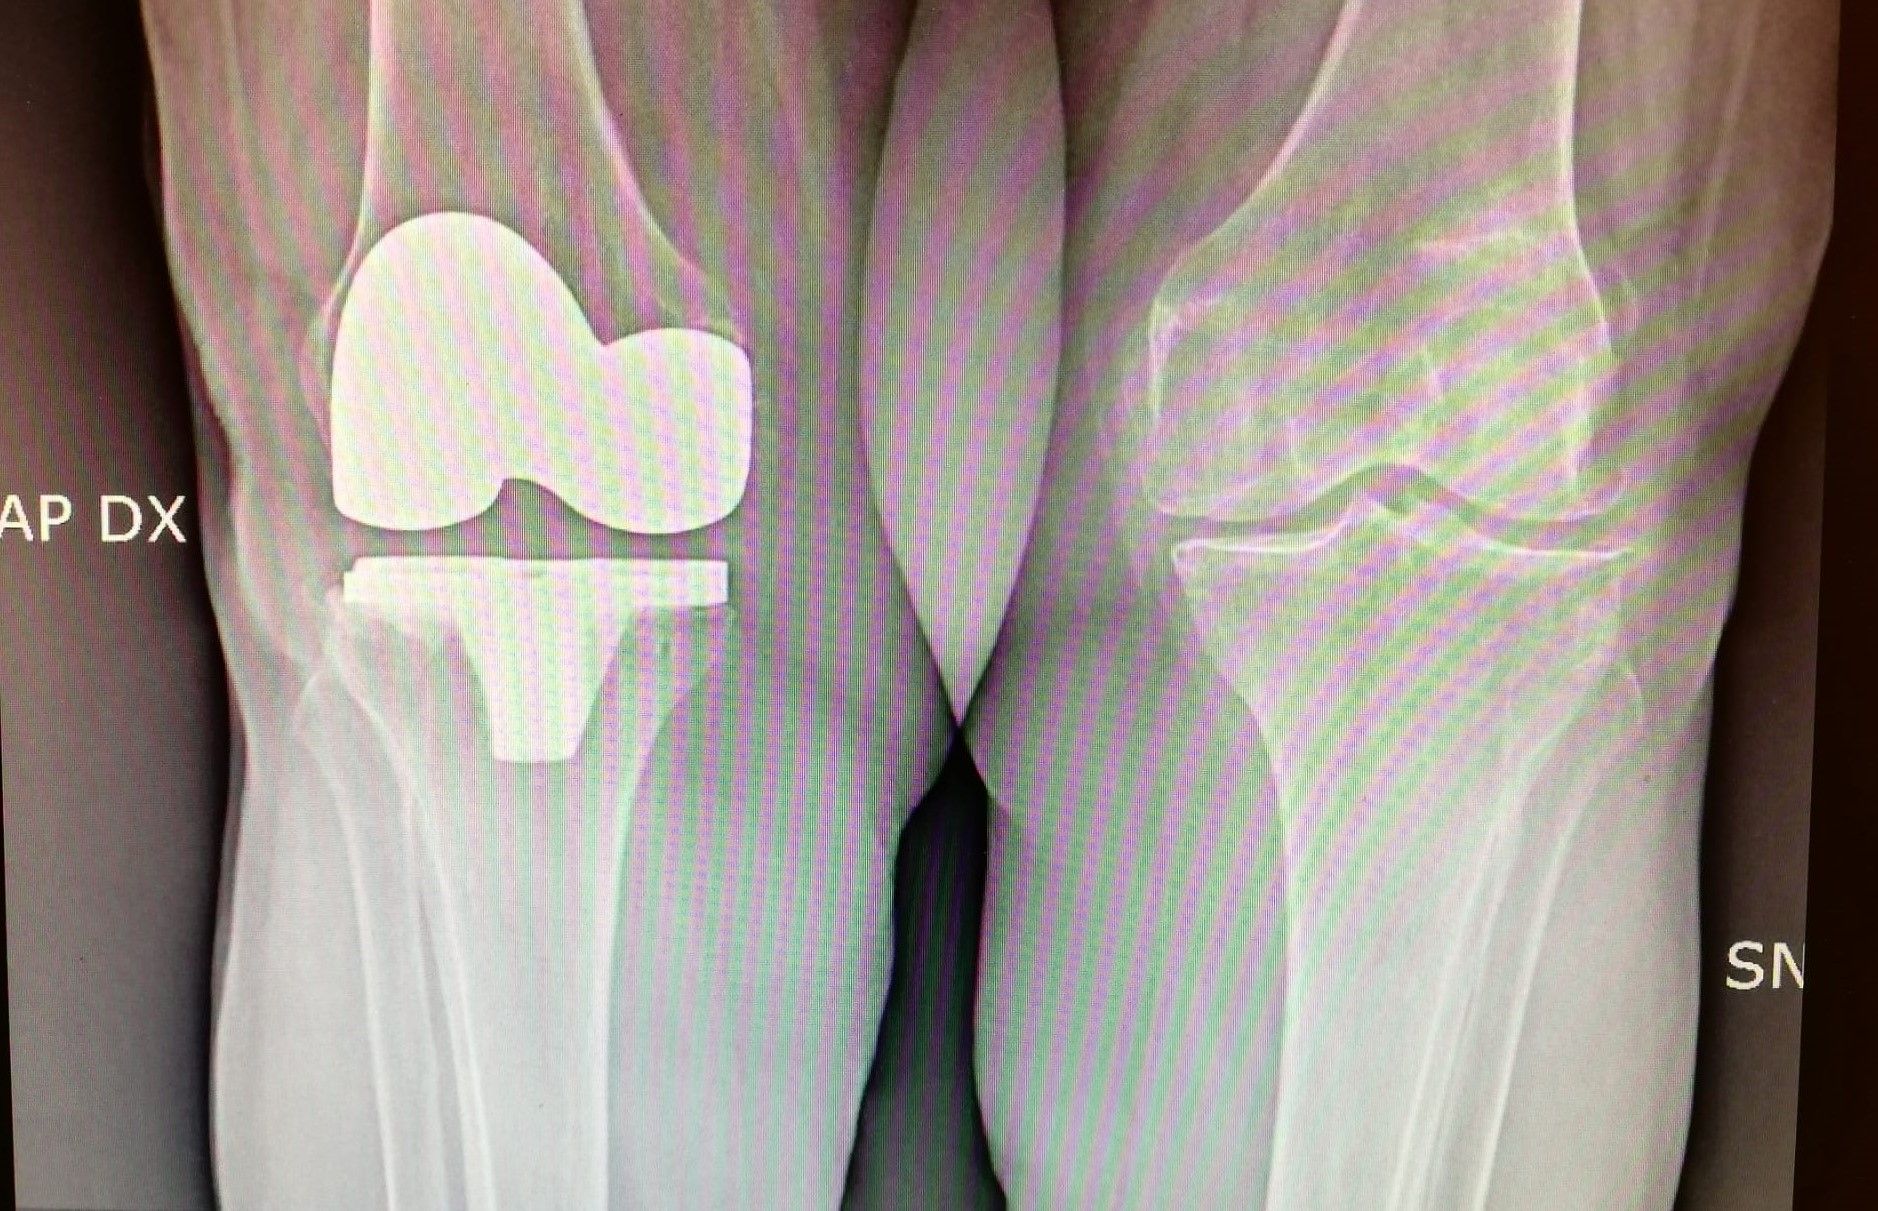

La protesi di ginocchio è costituita da una componente tibiale, una femorale, entrambe in lega di cromo-cobalto, ed un inserto in polietilene che aumenta la congruenza articolare e la stabilità dell’impianto protesico. In genere, le componenti protesiche si fissano all’osso con il cemento, oppure utilizzando degli impianti in tantalio, materiale che si osteointegra completamente entro 3 mesi, senza necessità di cementare.